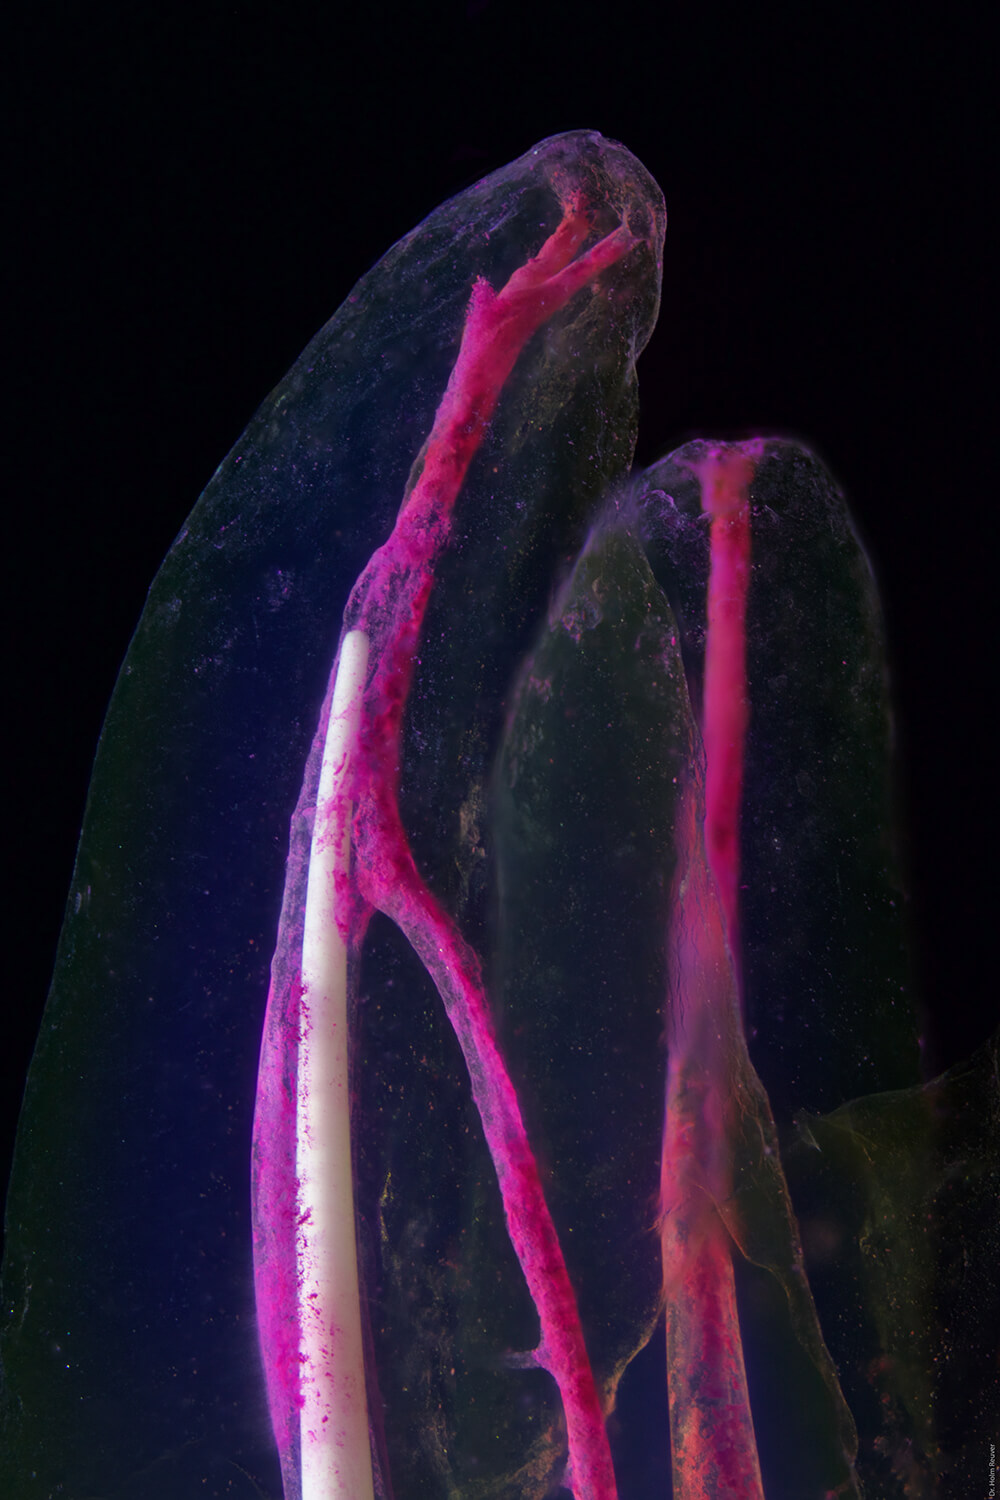

Abbildung 3:

Drei Wurzelkanäle eines oberen Backenzahns. Das schneeweiße Instrument ist ein wahres Zauberwerkzeug zur gründlichen Reinigung von Hohlraumanteilen, die von den mechanischen Feilen nicht erfasst werden. Das Instrument wird in Schwingung versetzt, wordurch die desinfizierenden Flüssigkeiten auch in versteckte Nischen der Pulpahohlräume trasnportiert werden.

Die starken Strömungen bewirken außerdem eine intensive Durchdringung der Zielsubstanzen (infiziertes Material) mit den Desinfektionsflüssigkeiten. Diese Unterstützung der Wurzelkanalpräparation ist für die Zähne sehr sanft und gleichzeitig extrem gründlich.